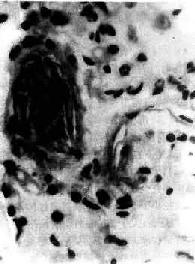

图3-9 肺羊水栓塞

小血管内有角化上皮 ×400